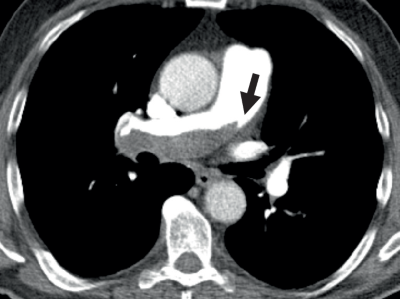

Tachykardie mit breiten QRS-Komplexen im EKG/© Trappe H-J et al. / all rights reserved Springer Medizin Verlag GmbH, Gastroskopie/© Lohmeyer JL et al. / all rights reserved Springer Medizin Verlag GmbH, Bewusstloser Mann/© chameleonseye / Getty Images / iStock (Symbolbild mit Fotomodellen), Kathetergestützte mechanische Thrombektomie /© Hecker M et al. / all rights reserved Springer Medizin Verlag GmbH, EKG-Kontrolle in einer Praxis/© Inside Creative House / Getty Images / iStock (Symbolbild mit Fotomodell), EKG auf Monitor/© sudok1 / Stock.adobe.com, Eine Frau zeiht Kompressionstrümpfe auf dem Teppich an/© dream@do / stock.adobe.com (Symbolbild mit Fotomodell), Person hält Tablette und Glas/© bilderstoeckchen / stock.adobe.com (Symbolbild mit Fotomodell), Frau hält Tabletten-Blister und Beipackzettel in der Hand/© Vladimir Vladimirov / Getty Images / iStock (Symbolbild mit Fotomodell), Medikamente und Medikationsplan/© Photographee.eu / stock.adobe.com, Zentrale Lungenembolie/© Springer Verlag Berlin Heidelberg 2015, Kaiserschnitt/© karegg / Stock.adobe.com (Symbolbild mit Fotomodellen), Älterer Mann schaut kritisch auf Tabletten/© Mediteraneo / stock.adobe.com (Symbolbild mit Fotomodell), Eine Person hält sich den Oberschenkel/© saran / Stock.adobe.com (Symbolbild mit Fotomodell), Chirurg führt Katheterablation durch/© Damian / stock.adobe.com (Symbolbild mit Fotomodellen), Älterer Mann mit Tabletten in der Hand/© vorDa / Getty Images / iStock (Symbolbild mit Fotomodell), EKG bei ventrikulärer Tachykardie/© Trappe H-J et al. / all rights reserved Springer Medizin Verlag GmbH, Heparin zur Antikoagulation/© Angel Arredondo / stock.adobe.com, Kolorektale Lebermetastase in Segment II, nahe der linken Lebervene (LHV)./© Sucher, E. et al. / all rights reserved Springer Medizin Verlag GmbH, Search Icon, FARAPULSE™ Joggende Frau im Park, Läuferin im Park/© PeopleImages / Shutterstock (Symbolbild mit Fotomodell); Boston Scientific Medizintechnik GmbH, Arzt erklärt Patient Operation am Laptop/© DC Studios / Adobestock (Symbolbild mit Fotomodellen), Arzt-Patienten-Gespräch, Junge Ärztin im Gespräch mit Patientin/© Parichat / Adobestock (Symbolbild mit Fotomodellen), FARAPULSE™ Joggendes Paar im Park/© JenkoAtaman / Adobe Stock (Symbolbild mit Fotomodellen); Boston Scientific Medizintechnik GmbH